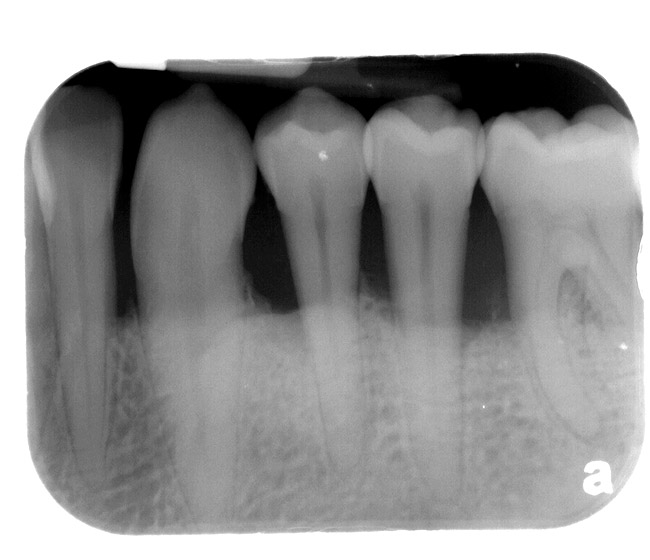

Bone loss is an indicator of past periodontal disease as well. Gustavo et al have established a guideline for percentage of bone loss relative to long-term prognosis.15 Bone loss percentage calculation was based on the total length of the root from the cemento-enamel junction to the apex minus approximately 2 mm (biologic width) to the length of the root supporting the alveolar bone. They divided bone loss into three categories < 30% (predictable),16,17 30% to 65% yellow (caution),18-20 and > 65% (consider extraction).13 This does not mean that all teeth with greater than 65% of bone loss need to be extracted; rather, teeth in this category as a whole have a poorer prognosis than teeth with less than 65% bone loss.